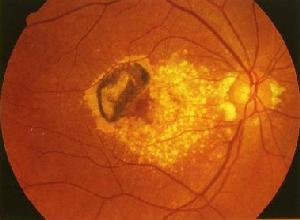

帶狀角膜病變:主要累及前彈力層的表淺角膜鈣化變性,常繼發於各種眼部或系統性疾病。病變起始於瞼裂區角膜邊緣部,在前彈力層出現細點狀灰白色鈣質沉著,病變外側與角膜緣之間有透明的角膜分隔,內側呈火焰狀逐漸向中央發展,匯合成一條帶狀混濁,橫過角膜的瞼裂區。沉著的鈣鹽最終變成白色斑片狀,常高出於上皮表面。可出現視力下降,異物感,角膜上皮缺損等,有時伴有新生血管。

角膜帶狀變性(band degeneration of cornea )又名角膜帶狀病變(band ker-atopathy)。角膜帶狀變性是發生於瞼裂部位的角膜暴露區,表現在角膜上皮層下前彈力層處呈灰色帶狀混濁。混濁首先發生在3點和9點處角膜緣,與角膜緣周邊相隔一狹窄透明區。然後混濁由兩側向中央擴展,最終連線,形成中部狹窄、兩端較寬、橫貫瞼裂的帶狀混濁區。病變部位常伴有鈣質沉著的白色鈣化斑。最後病變可侵犯到角膜基質層和出現新生血管。晚期可出現刺激症狀。本病常為絕對期青光眼、葡萄膜炎和角膜炎後的併發症,也可發生在已萎縮的眼球上。亦可見伴有高血鈣症的全身病(如維生素D中毒、副甲狀腺功能亢進等);與遺傳有關的原發性帶狀角膜病變較為少見。